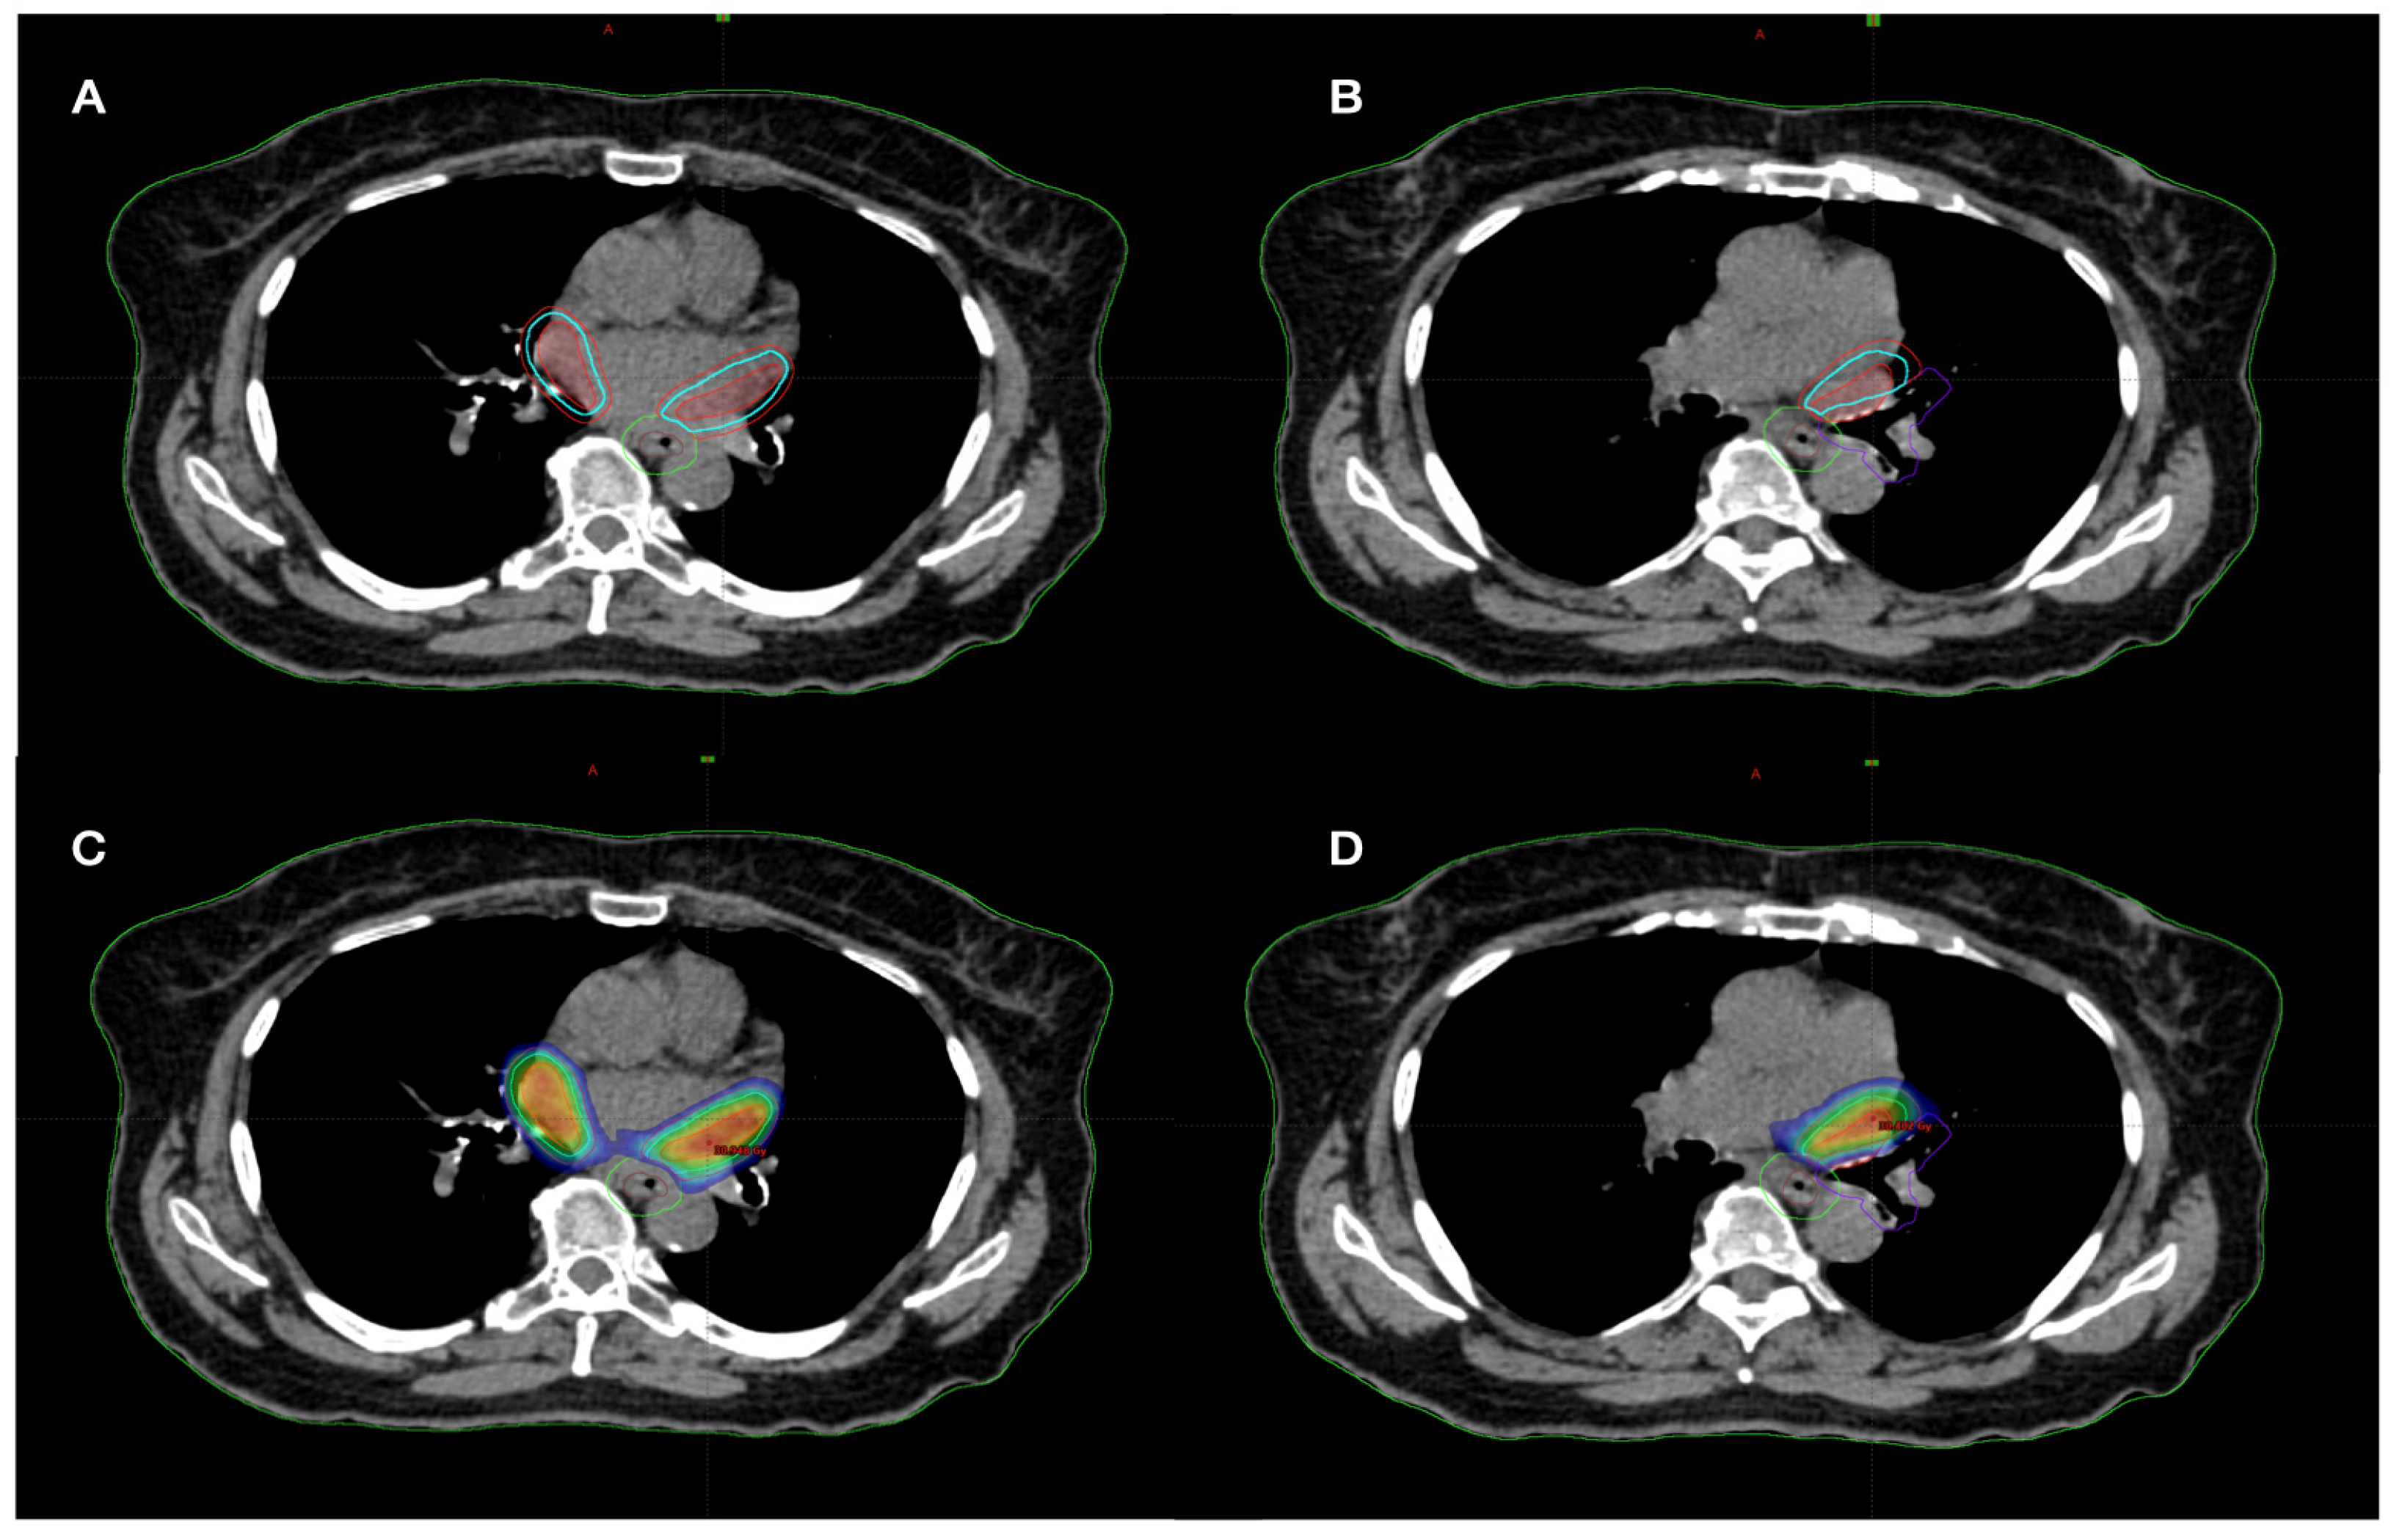

Figure 2.

(A,B) PTV and ITV cropped from OaRs (esophagus and bronchus); (C,D) STAR Planning with simultaneous integrated protection dose.

Medial-lateral (M-L), anterior-posterior (A-P) and superior-inferior (S-I) displacements for the center of mass of CTVright and CTVleft were evaluated during all respiratory phases on 4D-CT. STAR was performed in free-breathing, prescribing 25 Gy in single fraction. A “simultaneous integrated protection” (Figure 2) dose was realized to the interface between PTV-PRV to ensure the tolerability of critical structures [16]. To avoid dose hotspots in the ITV-PTV expansion, it was decided to prescribe the dose to ITV volume, with an additional PTV dose coverage of 95% dose to 95% of the volume.

As the first aim of the trial was to prevent grade 3 toxicities, PTVs were cropped to the PRV of OaRs (Figure 2), so in this way, all dose constraints, in terms of maximal dose for OaRs, were respected [15,17].

Since there are no other analyses in the literature about the use of LINAC for AF-STAR, we could only compare these results with a few published cases performed with a different technology (Cyberknife) [18,19]. As previously reported, the target definition was not the same. In the Cyberknife cases, the PVs and the left atrial posterior wall were irradiated. The mainstay AF ablation approach is PVs isolation, while appropriate/effective ablation targets, including the atrial wall, remain poorly defined [1,18,19]. Thus, in the present trial, the target was defined as the area around the PVs, defined by radiation oncology and cardiology (Figure 1 and Figure 2). In fact, the present mean CTV was 23 cc, while for Cyberknife, data is roundly 50 cc for all cases.

Based on the targets (2 PTVs for each patient, Figure 1), a 10MV-FFF VMAT plan with three coplanar or non-coplanar arcs is useful in order to obtain better target coverage, sparing OaRs, as shown in Table 2 and Table 3. Surely, considering the “protection of OaRs” and the dose prescription on ITV, the conformity index calculated on PTV was higher than 1, but acceptable (range 1–1.99).